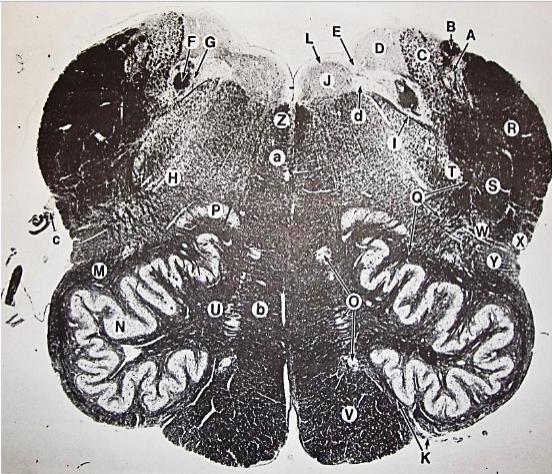

A

fasciculus gracilis

B

gracile nucleus

C

fasciculus cuneatus

D

cuneate nucleus

F

internal arcuate fibers

G

decussation of internal arcuate fibers

H

medial lemniscus

I

hypoglossal nucleus

J

dorsal motor nucleus vagus

K

solitary fasciculus

L

solitary nucleus

M

dorsal longitudinal fasciculus

N

spinal trigeminal tract

O

spinal trigeminal nucleus

P

posterior spinocerebellar tract

Q

anterior spinocerebellar tract

R

spinal lemniscus

S

lateral vestibulospinal tract

T

rubrospinal tract

U

lateral reticular nucleus

V

medial accessary olivary nucleus

W

pyramidal (corticospinal) tract

X

arcuate nucelus

Y

medial longitudinal fasciculus

Z

tectospinal tract

a

fascicles of hypoglossal nerve